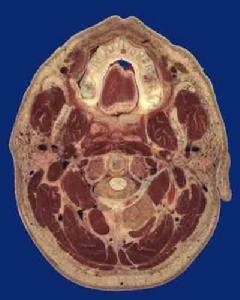

枕靜脈2.層次覆蓋於此區的軟組織,由淺入深依次為:皮膚、淺筋膜、帽狀腱膜及枕額肌、腱膜下疏鬆組織和顱骨外膜。其中,淺部三層緊密連線,難以將其各自分開,因此常將此三層合稱“頭皮”。深部兩層連線疏鬆,較易分離。

(1)皮膚:此區皮膚厚而緻密,並有兩個顯著特點,一是含有大量毛囊、汗腺和皮脂腺,腫或皮脂腺囊腫的好發部位;二是具有豐富的血管,外傷時易致出血,但創口癒合較快。

(2)淺筋膜:淺筋膜內的血管和神經,可分為前、後兩組。前組:距正中線約2cm處,有滑車上動、靜脈和滑車上神經。距正中線約2.5cm處,尚有眶上動、靜脈和眶上神經。兩動脈均為眼動脈的終支;伴行靜脈末端匯合成為內眥靜脈;同名神經為三叉神經第一支眼神經的分支。後組:有枕動、靜脈和枕大神經等,分布於枕區。枕動脈為頸外動脈的分支;枕靜脈匯入頸外靜脈;枕大神經來自第2頸神經的後支。由於顱頂的神經分布互相重疊,故在局部麻醉時,如僅阻滯一支神經,常得不到滿意效果,而需擴大神經阻滯的範圍。

(3)帽狀腱膜:前連枕額肌的額腹,後連枕腹,兩側逐漸變薄,續於顳筋膜。頭皮裂傷,伴有帽狀腱膜橫向斷裂時,因枕額肌的收縮,創口裂開較大。縫合頭皮時,應將腱膜仔細縫合,以減少皮膚張力,有利於創口的癒合。

結締組織

枕靜脈由緻密結締組織構成,借少量結締組織與顱骨表面相連,二者易於剝離。嚴重的頭皮撕脫傷,可將頭皮連同部分骨膜一併撕脫。骨膜與顱縫緊密愈著,骨膜下血腫,常局限於一塊顱骨的範圍內。